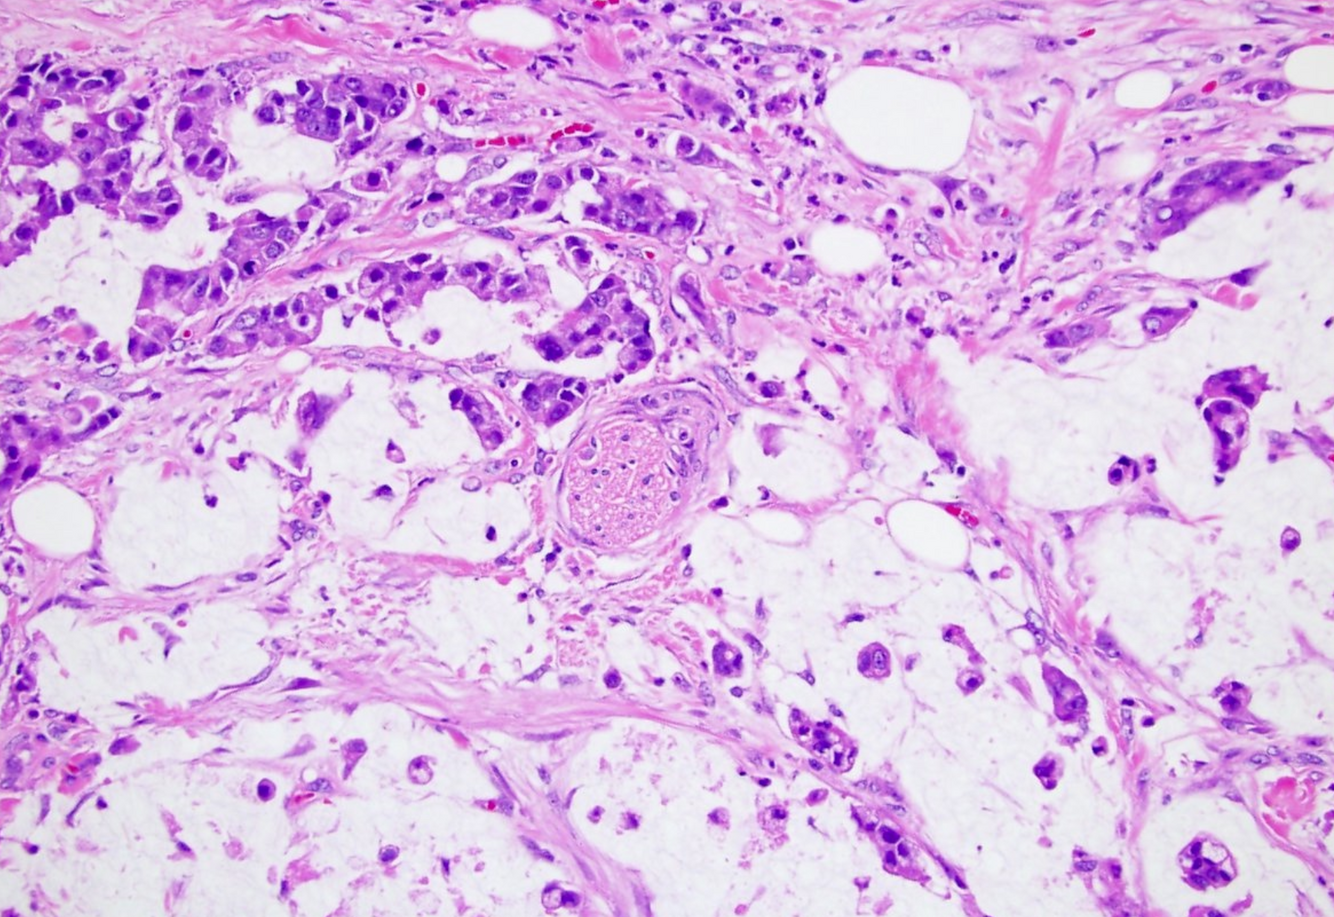

Invasive urothelial carcinoma, or “the tumor formerly known as ‘transitional cell carcinoma’”

Most arise within the setting of either high-grade papillary urothelial carcinoma or flat carcinoma in-situ.

Characterized by irregular tongues of cells or single cells pushing into the lamina propria. “Paradoxical differentiaton” is often present. A retraction artifact separating the stroma from tumor nests is present in H&E preparations. There may or may not be a desmoplastic response.

Paradoxical differentiation

Seen in invasive urothelial carcinoma/transitional cell carcinoma

The deep invasive cells acquire increased pink cytoplasm, mimicking mature surface cells.

Identifying ___ is critically important in invasive urothelial carcinoma.

Identifying the muscularis propria/detrusor muscle is critically important in invasive urothelial carcinoma.

Superficial tumors that do not invade the muscularis propria are treated conservatively by transurethral resection or topical chemotherapy/brachytherapy.

Invasion of the muscularis propria buys the patient a cystectomy.